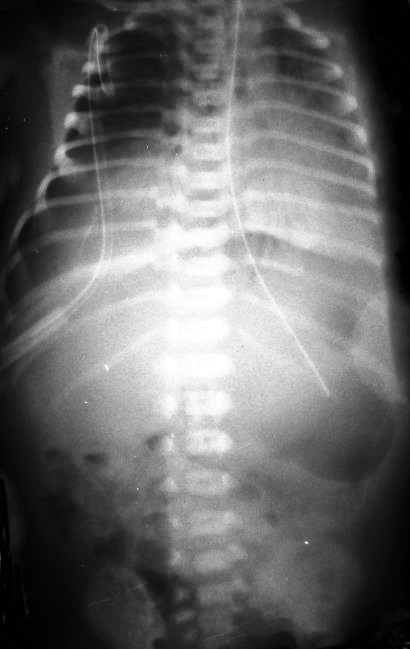

Ребенок Т. поступил 01.09.2017 в отделение реанимации новорожденных НОДКБ на 9-е сут жизни (дата рождения 23.08.2017) с диагнозом: внутриутробная инфекция, врожденная пневмония, дыхательная недостаточность III ст., синдром дыхательных расстройств, перинатальное поражение центральной нервной системы (ЦНС), синдром угнетения, судорожный синдром, кардиопатия, анемия. Ребенок от третьей беременности на фоне вазомоторного ринита, гипотиреоза, носительства вирусов герпеса и цитомегаловируса. Пренатально патологии не выявлены. Вторые роды на сроке гестации 40 недель в головном предлежании. Околоплодные воды светлые. Оценка по шкале Апгар 8/9 баллов. Через 1,5 ч после рождения состояние ребенка ухудшилось из-за дыхательной недостаточности. На 3–4-е сут жизни развился судорожный синдром. На 4–5-е сут – признаки желудочного кровотечения. При поступлении в НОДКБ состояние очень тяжелое, уровень сознания – кома I–II степени, признаки дыхательной недостаточности, недостаточности кровообращения, анемии тяжелой степени. В легких дыхание жесткое, равномерное, выслушиваются крепитирующие хрипы, усиливающиеся справа. Тоны сердца глухие, ритмичные. Живот мягкий, доступен пальпации. По желудочному зонду патологического отделяемого нет. По УЗИ органов брюшной полости без патологии, на рентгенографии легких признаки правосторонней пневмонии. В динамике появилась реакция на осмотр, спонтанная двигательная активность, снижение параметров искусственной вентиляции легких (ИВЛ). На 3-и сут пребывания в стационаре развился напряженный пневмоторакс справа (рис. 2), выполнено дренирование правой плевральной полости по Бюлау, «сброс» воздуха постоянный, в связи с чем ребенок переведен на высокочастотную ИВЛ, на фоне которой удалось купировать сброс и явления пневмоторакса (рис. 3). После этого ИВЛ в режиме SIMV. На 7-е сут удален плевральный дренаж. К 24-м сут жизни состояние ребенка стабилизировалось, питание усваивал, сохранялся лейкоцитоз с нейтрофильным сдвигом влево.

Рис. 2. Рентгенограмма органов грудной клетки. Картина напряженного пневмоторакса справа, обращает на себя внимание лабильность правого купола диафрагмы.